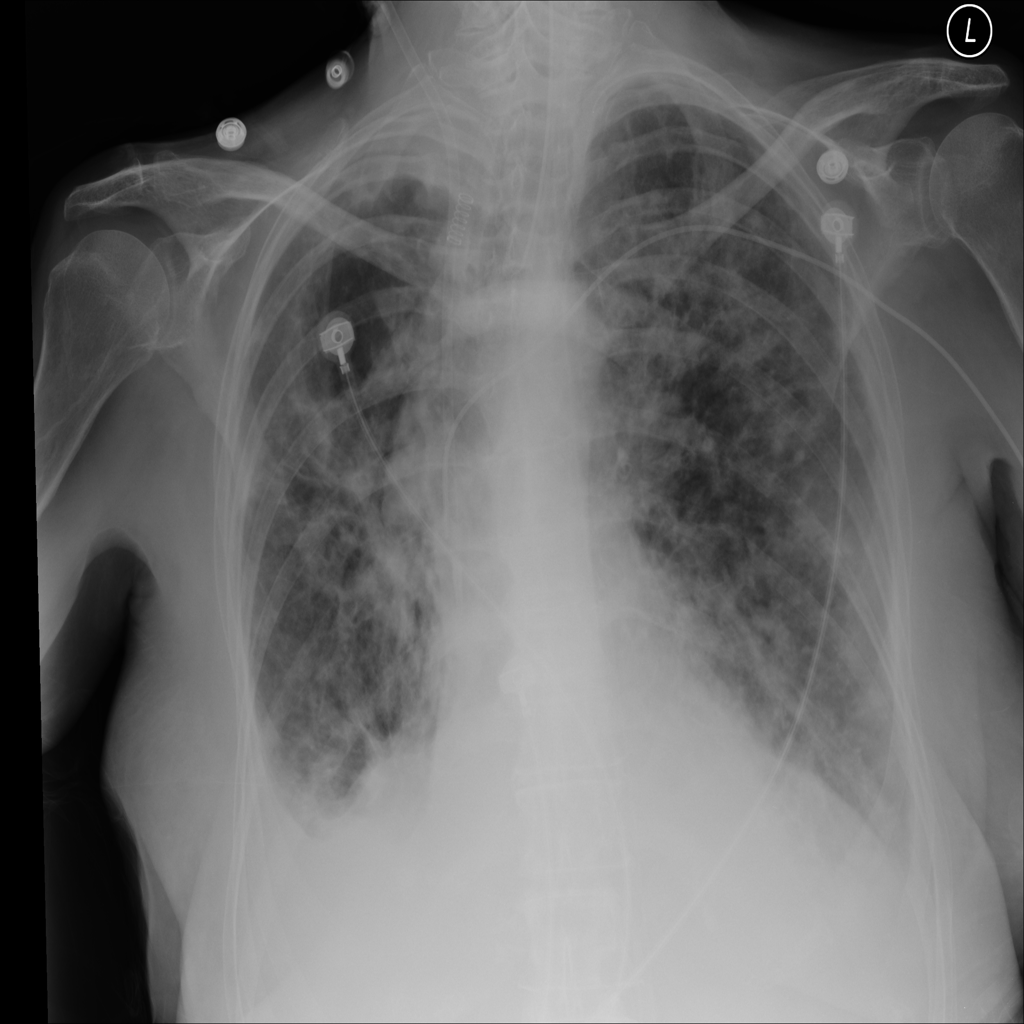

PAT-1F50 · IMG-000Fibrosis

PAT-1F50 · IMG-000

PA